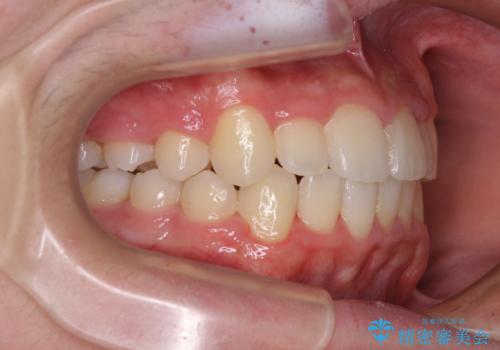

中学生のワイヤー矯正 クロスバイトを短期間で改善

叢生のため磨き残しの多い歯列でしたが、1年弱で治療を終了でき、磨き残しや歯肉の腫れが著しく改善されました。